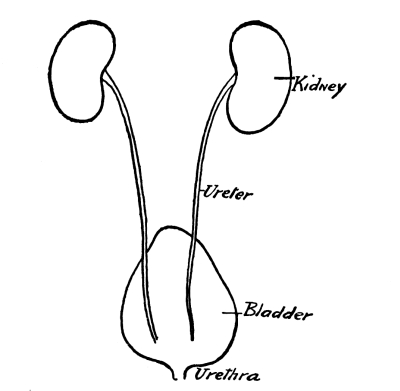

The Abdominal Cavity, 132—Muscles of the Abdomen, 132—The Peritoneum, 134—Abdominal Regions, 134—Salivary Digestion, 136—The Pharynx, 139—The Esophagus, 138—The Stomach, 138—Gastric Digestion, 139—Vomiting, 140—Intestinal Canal, 141—The Small Intestine, 142—Intestinal Digestion, 143—Absorption in Intestine, 144—The Large Intestine, 145—Food and Metabolism, 147—The Liver, 149—The Gall-bladder, 152—The Pancreas, 153—The Spleen, 153—The Suprarenal Capsules, 154—The Kidneys, 155—The Urine, 156—The Ureters, 159—The Bladder and Urethra, 159. |